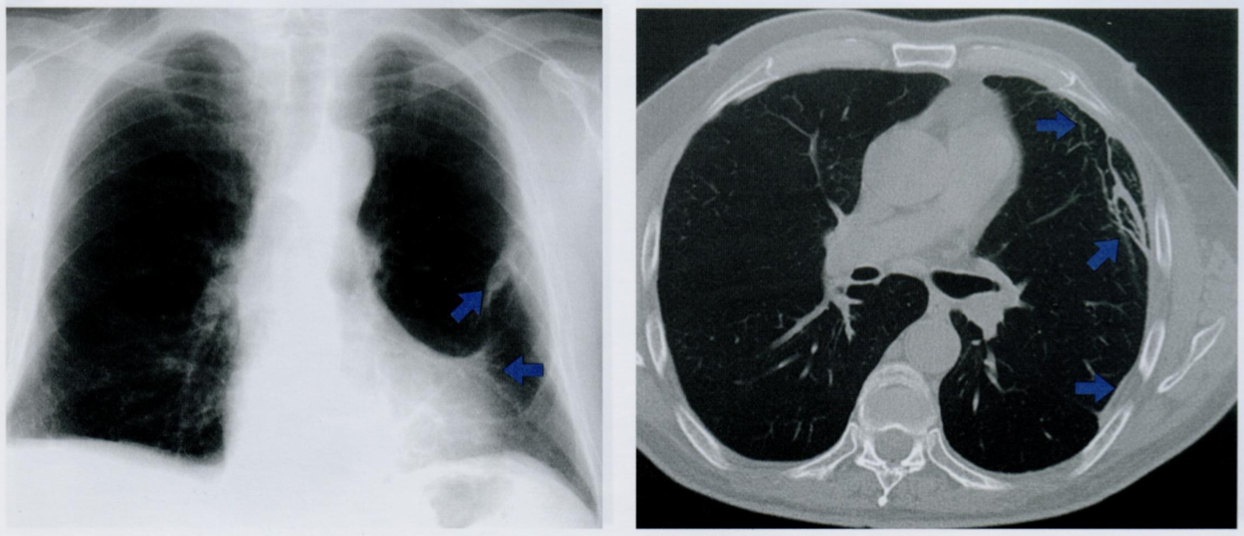

Плевральные бляшки представляют собой очаговые утолщения париетальной плевры. Они состоят из скопления гиалинизированных коллагеновых волокон, почти всегда образующихся в результате асбестозной пролиферации.

На снимке показано утолщение плевры при асбестозе и плевральные шварты (стрелки).

Результаты КТ на подтверждают наличие фиброзных изменений (стрелки) на плевре латерально с левой стороны с множественным распространением на междольковые перегородки.

Варианты асбестоза плевры представлены на схеме.